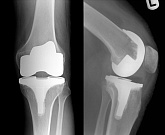

Еndoprosthesis of knee joint

In the late stages of arthrosis of the knee joint, accompanied by a pronounced restriction of the volume of movements, constant intense pain, deformity of the limb, the only way to recover is to replace the affected joint with an artificial joint - arthroplasty.

This method allows you to return the correct form of the limb, the full volume of movements in the joint, relieve the constant pain and crunch during movements and, as a result, significantly improve the patient's quality of life.

Below are presented X-ray photographs and photographs, illustrating the amount of motion in the affected joint before and after surgery.